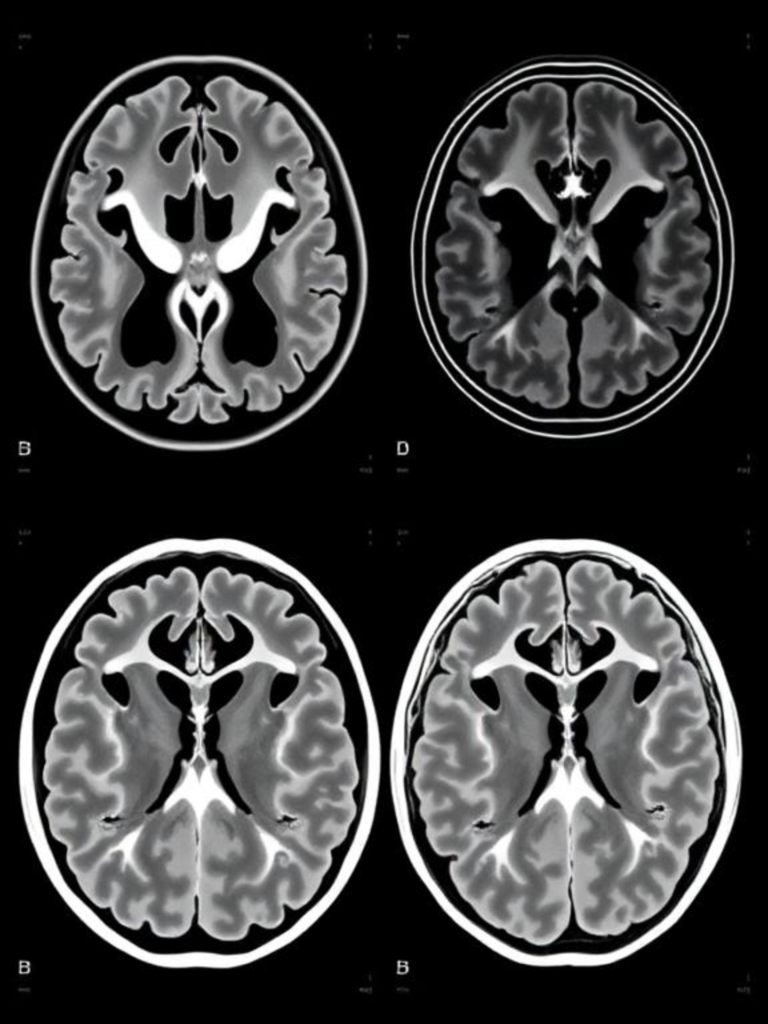

MRI and Brain Imaging in Diagnosis

Although brain imaging techniques like MRI and fMRI are valuable in research, they are not yet routinely used for diagnosing mental illnesses due to limited specificity and high costs.

MRI (Magnetic Resonance Imaging) is a non-invasive imaging technique widely used for accurate diagnosis of neurological and mental health related conditions